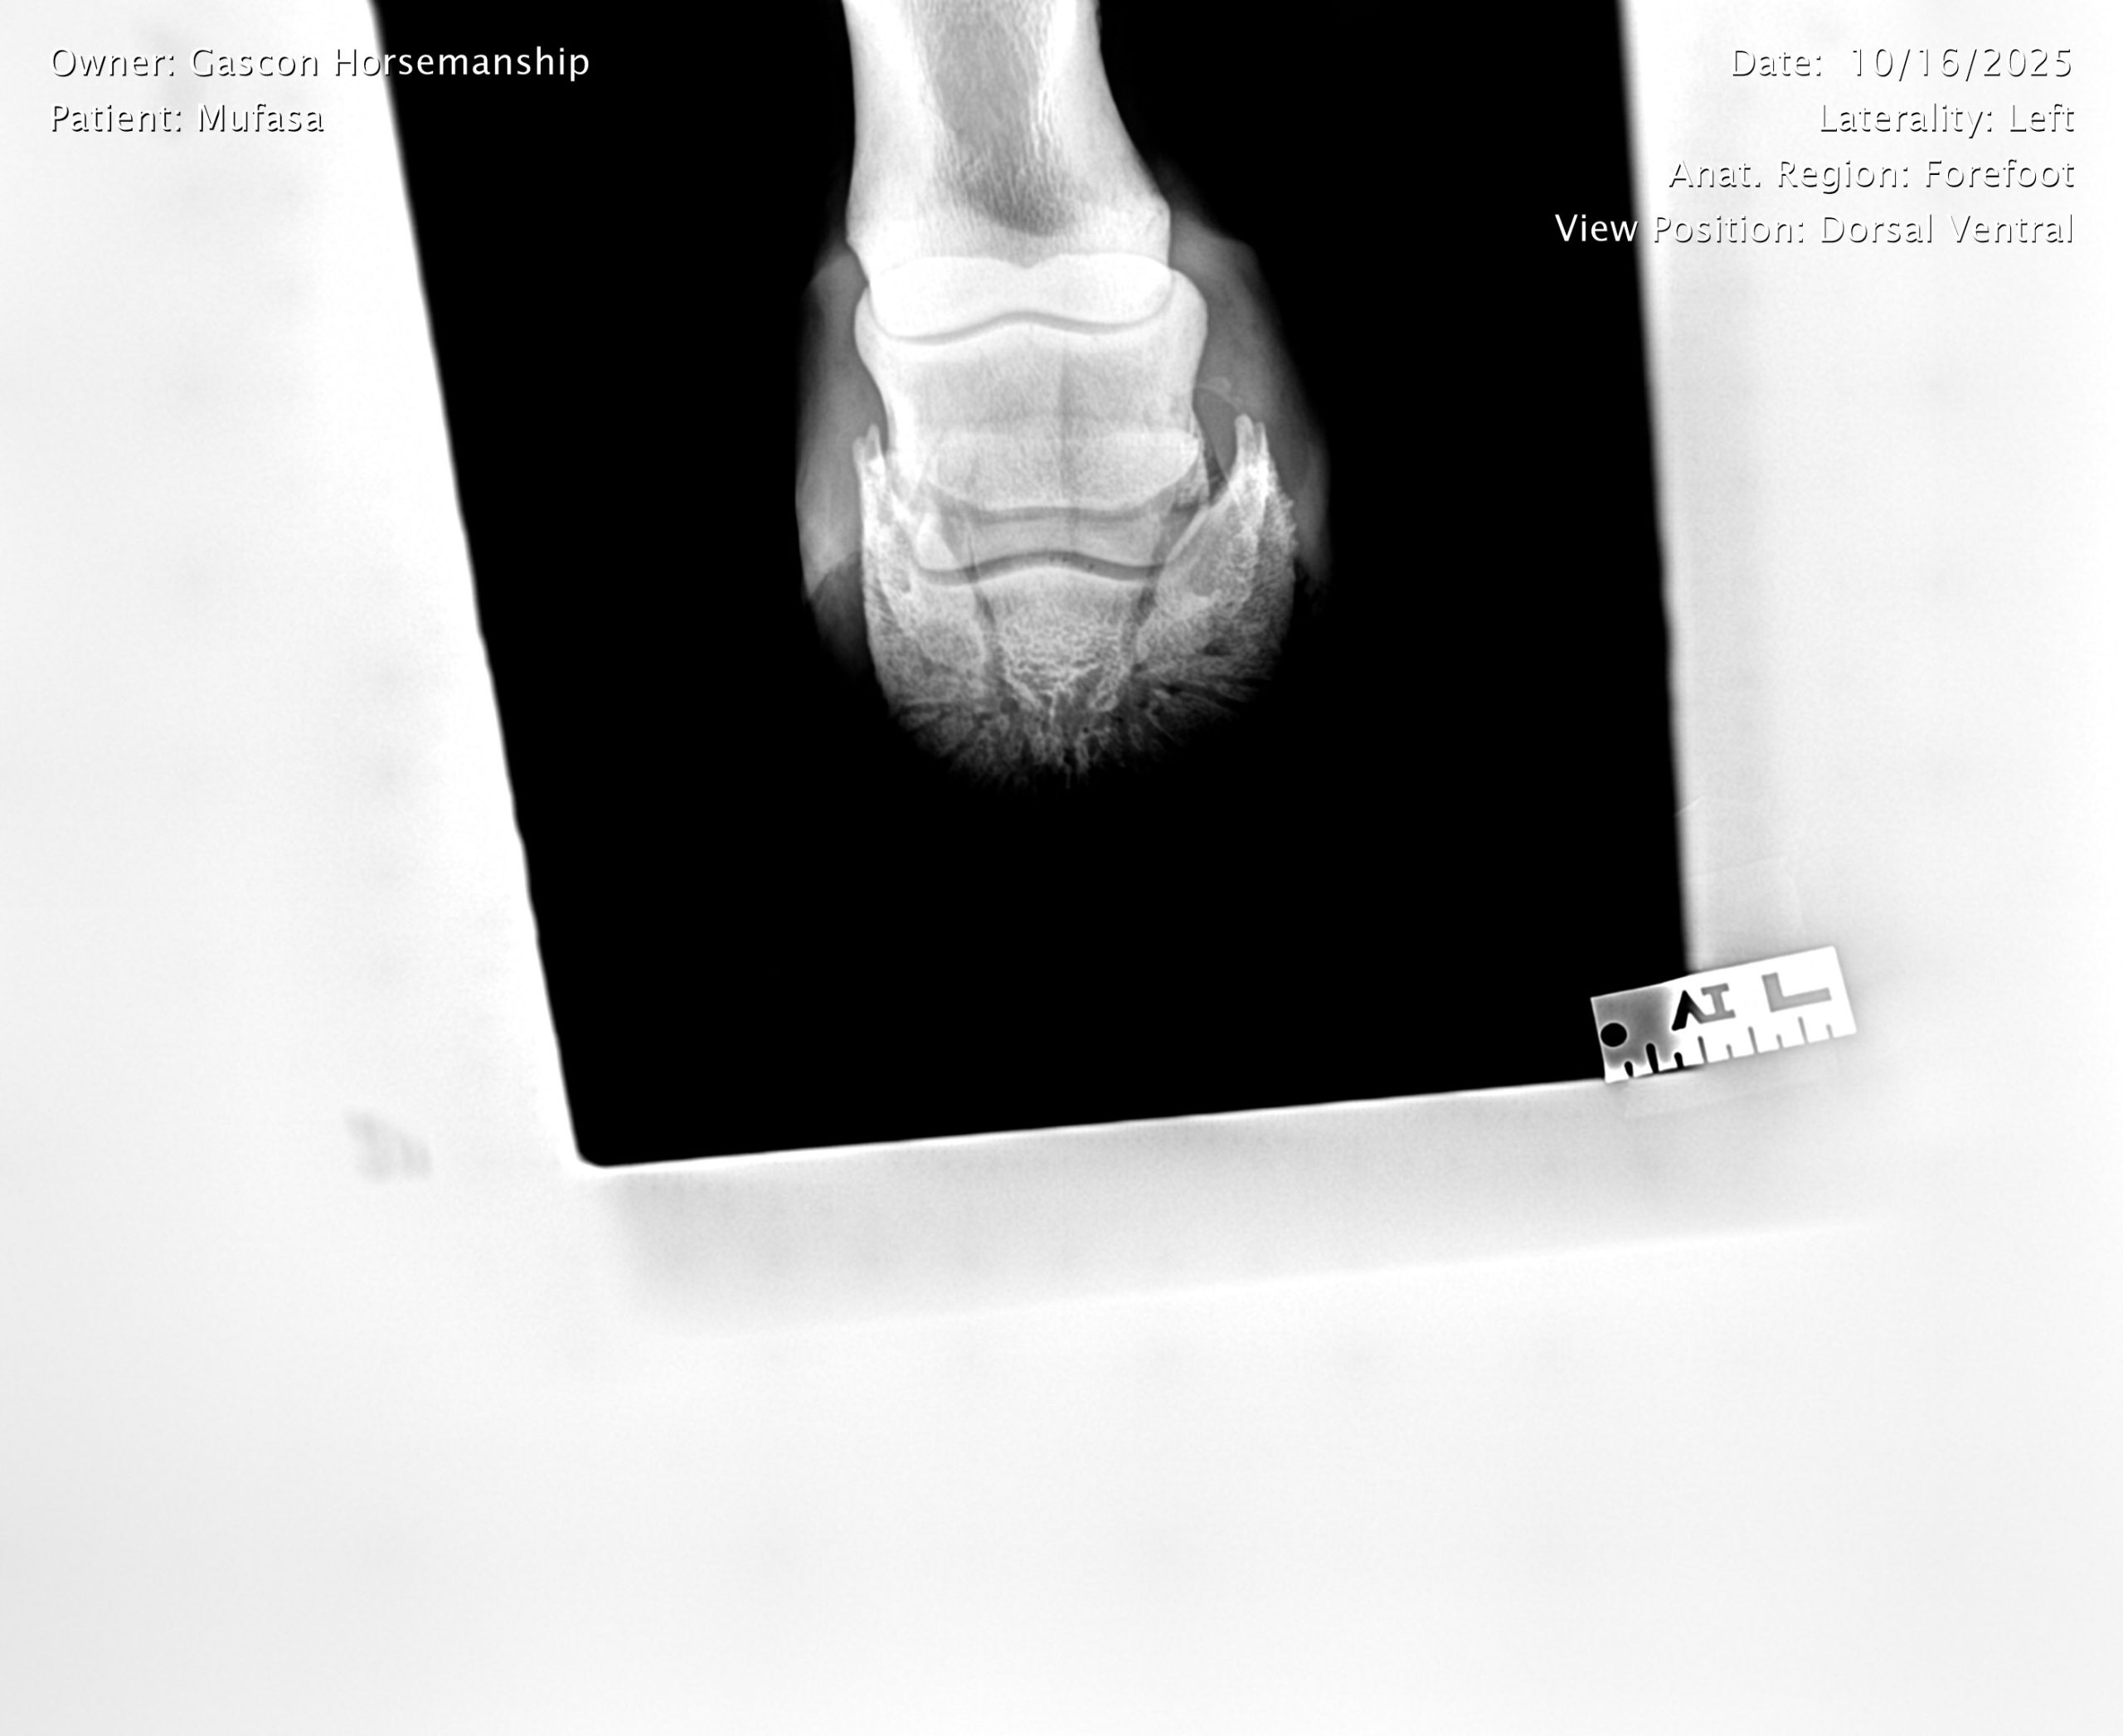

He already has a full pre-purchase exam on file, complete with 25 X-rays included in his album.